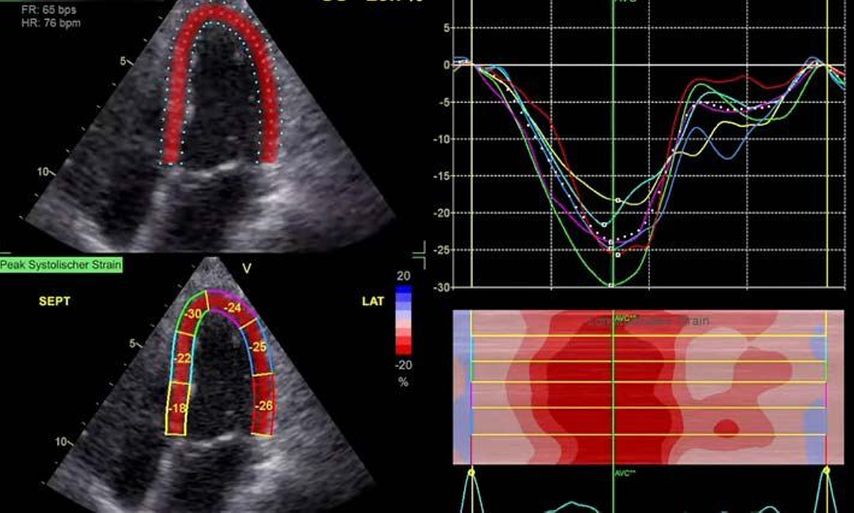

Die moderne Echokardiografie bietet die Möglichkeit einer hämodynamischen Evaluation in Ruhe wie auch bei „point-of-care“-Belastung. „Strain imaging“ und „myocardial work“ können neben bekannten Parametern, wie der Ejektionsfraktion (EF) und der Myokardmasse, ergänzend zur Diagnostik von Herzerkrankungen beitragen.

Moderne Messparameter wie „strain imaging“ geben diagnostische und prognostische Information.

Im Echolabor des Pyhrn-Eisenwurzen Klinikums Steyr wird jede Form der Myokardwandverdickung mittels einer vollständigen Standardechokardiografie untersucht.2 Dabei wird auch ein Fokus auf die kontrastmittelunterstützte Sonografie gelegt, um die tatsächliche Dicke des Myokards zu vermessen.3 Die Verdickung sollte optimalerweise mittels 3D-LV-Massenmessung erfolgen. Die Messung im 2D-Bild ist dahingehend unterlegen. Ebenso wird jede Myokardwandverdickung mittels 2D-„strain imaging“ in der transthorakalen Echokardiografie (TTE) untersucht.4–6 Der „strain“ ist eine Messung der longitudinalen Funktion des Herzens (Video 1).

Der erste Fall beschäftigt sich mit einem Patienten mit einer hypertrophen Kardiomyopathie (HCMP). Er gibt eine deutliche Belastungsdyspnoe sowie einen ausgeprägten Leistungsknick an. Es wurde infolgedessen eine Untersuchung mittels standardisierter Echokardiografie inklusive „strain imaging“ durchgeführt. Der globale longitudinale „strain“ (GLS) mit –16% in Ruhe war gering reduziert. Es konnte kein relevanter LVOT-Gradient in Ruhe nachgewiesen werden. In der Belastungssituation (Handgrip, Valsalva, Kniebeugen und als Vorbereitung zur Untersuchung ein ausgiebiges Frühstück und Kaffee sowie ein am Vorabend konsumiertes Bier) konnte bei Kniebeugen mit einer Herzfrequenz von 126/min ein Spitzengradient bis 52mmHg dargestellt werden. Somit ergibt sich die Diagnose einer HOCMP mit einem belastungsinduzierten Gradienten. Bei bereits bestehender und ausgereizter Therapie unter Betablocker besteht die Indikation zur Therapie mittels des kardialen Myosininhibitors Mavacamten (Klasse-IIa-Empfehlung laut ESC).1 Darunter verbesserte sich die klinische Situation des Patienten deutlich, der Patient konnte uneingeschränkt Sport ausüben. Über die Zeit kam es zu einer geringen Reduktion der LV-Masse und einer geringen Zunahme des LV-„strain“. Die Belastungssituation zeigte durchwegs normale „strain“-Werte mit –20% (mit regionaler Reduktion bei Myokardwandverdickung im Sinne einer Hypertrophie). Die myokardiale Arbeit beim konkreten Patientenfall ist ebenso in Ruhe im grenzwertigen und unter Belastung im guten Normalbereich.6,8,9 Der Patient ist derzeit unter 5mg Mavacamten einmal täglich optimal eingestellt. Die EF in Ruhe ist konstant bei 50–55%. In Video 2 werden unterschiedliche Gradienten dargestellt, um eine HOCMP mit LVOTO von z.B. einer Mitralklappeninsuffizienz zu unterscheiden.Die Verdachtsdiagnose wurde mithilfe der Echokardiografie gestellt und durch das septal betonte „patchy“ LGE im MRT bestätigt.1,5

Andere Formen der Myokardwandverdickung, die mit „strain“ und MRT gut dargestellt werden können, sind einerseits die Differenzierung der Auswirkung der arteriellen Hypertonie (weiblich, 72a) bei Vorliegen einer Herzinsuffizienz mit normaler EF, einem GLS von –15,4%, einem LA-„strain“, in Reservoirphase 25% bei gering verlängerten T1-Zeiten im MRT. Andererseits kann Steroidabusus (männlich, 44a) zu einem reduzierten „strain“ mit gering verlängerten T1-Zeiten und einer Normalisierung der bildgebenden Befunde nach 2 Jahren nach Absetzen führen bzw. eine Mitochondriopathie (männlich, 32a) zu einer unklaren Myokardverdickung mit diffus reduziertem „strain“ und reduzierter LV-Funktion.4,11,12